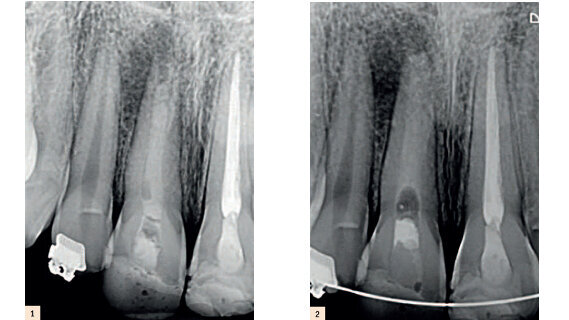

Un patient de sexe masculin de 12 ans, s’est présenté pour un examen, en se plaignant principalement d’une douleur à la dent 11. L’examen clinique a montré que la dent avait été restaurée avec un remplissage temporaire et réagissait douloureusement à une percussion et à une palpation et qu’il existait également un oedème discret à cet endroit. Il n’y avait pas de défaut de sondage fuite de matériau au niveau sinusal. Selon le patient, un traitement du canal radiculaire avait été commencé plus ou moins 12 mois plus tôt. Lors de l’examen radiographique, un matériel radio opaque à l’intérieur du canal à quelques millimètres de l’apex pouvait être observé. De surcroît, on pouvait voir sur la radiographie que l’apex n’était pas entièrement formé et présentait une lésion périapicale (Fig. 1). Le diagnostic clinique de dent sans vitalité avec thérapie préalablement commencée et périodontite apicale symptomatique a été établi.

Entre chaque changement d’instrument, une irrigation abondante avec une solution d’hypochlorite de sodium à 2,5 % a été utilisée (près de 100 ml tout au long du traitement). Durant la procédure, l’irrigation ultrasonique passive (PUI) a été réalisée durant 1 minute, plusieurs fois, afin d’assurer l’extraction complète du matériel d’obturation précédent et pour maximiser la technique d’irrigation. A la fin de la séquence instrumentale, le canal a été irrigué avec 5 ml d’EDTA à 17 % (Fórmula e Ação, São Paulo, État de São Paulo, Brésil) durant 3 minutes et une irrigation finale avec 5 ml de sérum physiologique. Une pâte à base d’hydroxyde de calcium a été mise en place dans le canal, comme un pansement entre les consultations et la dent a été temporairement restaurée (Fig. 2).